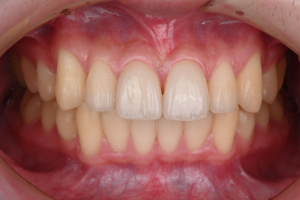

※治療終了時

歯並びが整い、あわせて形にバランスの乱れがあった上の前歯2本は、ラミネートベニアによって自然な見た目に整えられました。

※治療終了時の口腔内写真(正面)

歯科技工士が作製した補綴物は、周囲の歯になじむ自然な見た目に仕上がっています。